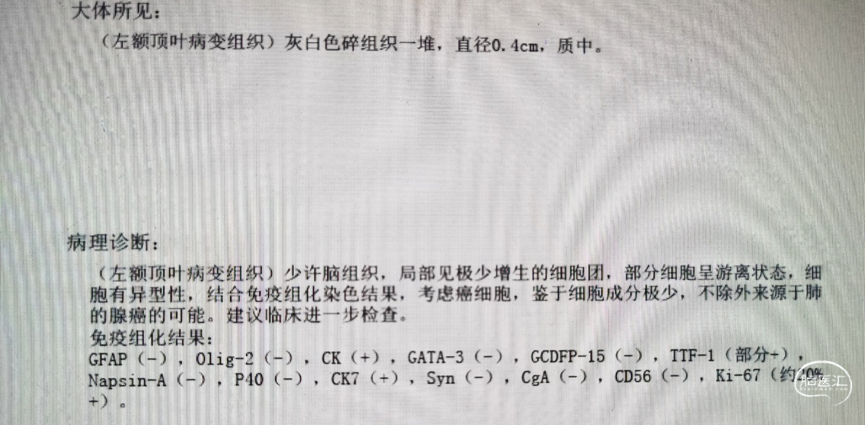

术后病理结果

立体定向穿刺活检+囊液抽吸+Ommaya囊植入,术中冰冻回报恶性肿瘤。

患者中老年女性,首发于颅内症状的脑转移患者,采用“立体定向穿刺活检+囊液抽吸+Ommaya囊植入+伽玛刀”的联合治疗方案,帮助患者明确了病理性质及来源,及时遏制了颅内多发病灶继续进展,以最小的创伤完成多发病灶的治疗,最大程度恢复了患者神经功能障碍,以最快的速度开始了靶向药物的全身系统治疗,显著提高了患者的生存质量,明显改善患者的预后生存。

脑转移瘤最常来源于肺癌、乳腺癌、恶性黑色素瘤、胃肠道恶性肿瘤、肾癌等恶性肿瘤,超过2/3的脑转移瘤在原发肿瘤诊断后1年内发生,是原发于颅内恶性脑肿瘤10倍还多。目前针对脑转移瘤的治疗主要包括开颅手术、放射治疗(包括立体定向放射外科治疗、全脑放疗)、全身系统治疗。